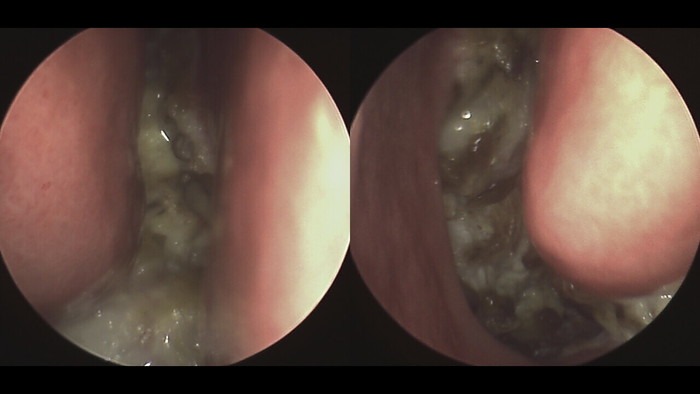

삼키는 것은 목, 입, 팔뚝 근육의 복잡한 상호 작용으로 인해 매일 수없이 수행되는 비자발적 행동입니다. 그러나 일부 개인의 경우 이러한 일상 활동에 불편한 통증이 동반될 수 있습니다. 이 포괄적인 탐구에서 우리는 삼킴의 생리학적 측면, 귀-목 연결, 통증의 일반적인 원인, 선별 접근법 및 효과적인 관리 전략을 탐구할 것입니다. 삼키는 생리적 과정과 귀 통증의 원인 삼키는 것은 목 근육의 활성화와 음식이나 타액의 식도로의 이동을 촉진하는 뇌에 의해 조정되는 반사 작용입니다. 이두근관은 입과 목 사이의 중요한 연결 역할을 하며 압력을 조절하고 때로는 통증을 유발합니다. 삼킬 때 구강 통증은 감기, 인후통, 중이염 등 다양한 요인으로 인해 발생할 수 있습니다. 이 상태가 목에 영향을 미치면 상호 연결된 이두근 관이 통증을 전달하여 삼키는 것이 불편한 경험이 될 수 있습니다. 귀, 목, 귀통증의 연관성과 특징적인 증상. 상구가 목에 가깝다는 것은 목의 문제가 이두근관을 통해 영향을 미쳐 목 상태와 지구 통증 사이의 연관성을 생성할 수 있음을 의미합니다. 종종 한쪽에서 삼키는 동안 구에 국한된 일시적인 통증이 이 상태의 특징입니다. 근본적인 원인을 파악하기 위해 의사를 만나는 것이 중요합니다. 진단 및 주요 질환 삼킬 때 입안에 통증이 느껴진다면 이비인후과 전문의의 진단이 필수적입니다. 인후염, 중이염, 이명, 편도선염, 후두염 등 다양한 상태가 이러한 불편함을 유발할 수 있습니다. 인후염 및 덩어리 통증: 인후염은 인후벽이 부어오르고 염증이 생기는 증상입니다. 이 염증이 심해지면 이두근관을 통해 통증이 전달될 수 있습니다. 이는 목과 귀 사이의 복잡하고 긴밀한 연결을 강조하여 한 쪽의 문제가 다른 쪽에도 영향을 미칠 수 있도록 합니다. 그러므로 인후통을 치료하고 통증을 완화시키는 것이 중요하며, 이를 위해서는 전문의의 도움을 받아 적절한 치료를 받는 것이 필요합니다. 중이염 및 통증 : 중이염은 중간 부분에 염증이 생기는 질환입니다. 귀의. 이때 이두박근이 막히면 귀의 압력을 조절하기 어려워져 통증을 유발할 수 있다. 이러한 상황에서는 귀의 생리학적 역할에 대한 이해가 필요합니다. 소리를 감지할 뿐만 아니라 균형을 유지해주기 때문에 정확한 압력을 유지하는 것이 중요합니다. 따라서 중이염을 효과적으로 관리하기 위해서는 중이염이 귀의 생리적 기능에 미치는 영향을 이해하고 적절한 치료를 받는 것이 중요합니다. 이명 및 통증: 이명은 귀에서 소리가 들리는 증상을 말합니다. 이러한 증상은 일시적일 수도 있고 지속적일 수도 있습니다. 심한 이명은 통증을 유발할 수 있습니다. 이는 청각 증상뿐만 아니라 그 증상이 미치는 광범위한 영향을 해결해야 할 필요성을 강조합니다. 이명이 심해지면 삶의 질을 떨어뜨릴 수 있으므로 전문가의 도움을 받아 적절한 치료를 받는 것이 중요합니다. 기타 귀, 목 질환 : 편도선염, 후두염 등의 질환도 통증을 유발할 수 있습니다. 이들 질환은 목이나 목 부위의 염증이 심해지면 이두근관을 통해 통증을 유발할 수 있다. 이는 귀와 목 사이의 상호 작용의 복잡한 특성을 보여 주며, 긴밀한 관계로 인해 하나의 문제가 다른 하나에 영향을 미칠 수 있습니다. 따라서 이러한 다른 질환들을 치료하여 통증을 완화시키는 것이 중요하며, 이를 위해서는 전문의의 도움을 받아 적절한 치료를 받는 것이 필요합니다. 광고 이후 계속됩니다. 다음 주제 작성자 삼킬 때 귀아픔 취소 재생 0 좋아요 0 좋아요 공유 0:00:00 재생 음소거 00:00 00:18 실시간 설정 전체 화면 해상도 자동 480p 자막 비활성화 재생 속도 1.0x(기본) 해상도 자동(480p ) 1080p HD 720p HD 480p 270p 144p 자막 설정 비활성화 옵션 글꼴 크기 배경색 재생 속도 0.5x 1.0x (기본값) 1.5x 2.0x 알 수 없는 오류가 발생했습니다. 도움말이 음소거되었습니다. 도움말 라이센스 이 영상은 고화질로 재생할 수 있습니다. 설정에서 해상도를 변경해보세요. 자세히 알아보기 0:00:00 접기/펼치기 삼킬 때 귀 통증 삼킬 때 귀 통증#침뱉기#귀 통증#중이염#인후통 치료 및 관리: 치료는 근본 원인에 따라 다르며 약물치료, 수술, 생활습관 변화 등이 포함될 수 있습니다. 포함될 수 있습니다. 효과적인 관리를 위해서는 전문가의 조언을 구하는 것이 중요합니다. 예방: 정기적인 검진, 습도 조절, 균형 잡힌 식단, 적절한 수분 섭취 등을 통해 전반적인 건강을 유지하면 삼킬 때 통증을 예방하는 데 도움이 됩니다. 결론 삼키는 동안의 통증을 이해하고 관리하는 것은 건강한 삶에 필수적입니다. 귀와 목 사이의 복잡한 연결을 인식하고 예방 조치를 취함으로써 개인은 이러한 불편함을 극복하고 전반적인 웰빙을 향상시킬 수 있습니다. 좋아요,댓글,댓글은 언제나 환영입니다. 함께 읽으면 좋은 글 https://blog.naver.com/kim_eunha/222928048841 어지럼증, 이명, 구토 증상이 있는 경우 먼저 귀를 확인해 보세요. 안녕하세요 건강톡톡 입니다. 안녕하세요 건강톡톡 입니다. 누구나 한 번쯤 경험해 볼 수 있는 것 중 하나가 어지러움… blog.naver.com